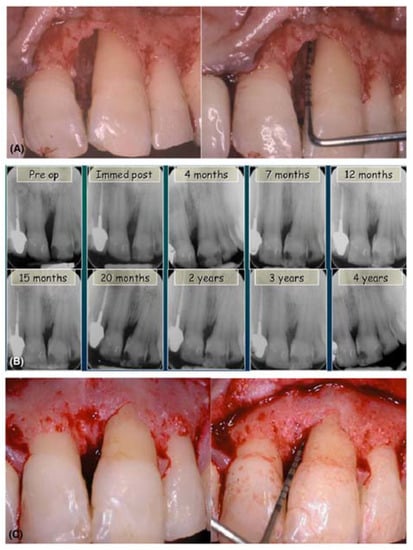

- Hägewald, S.; Spahr, A.; Rompola, E.; Haller, B.; Heijl, L.; Bernimoulin, J.P. Comparative study of Emdogain and coronally advanced flap technique in the treatment of human gingival recessions. A prospective controlled clinical study. J. Clin. Periodontol. 2002, 29, 35–41. [Google Scholar] [CrossRef] [PubMed]